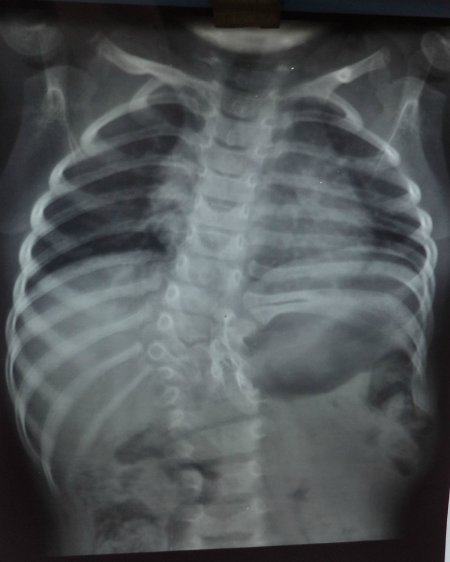

A 2-year-old girl presented with a swelling in left lumbar region noticed by parents one year back. The swelling gradually increased in size. It use to become more prominent on crying. On examination, there was a globular painless swelling (5cm x8cm)which was soft, reducible, and present below the left costal margin lateral to the dorso-lumbar spine (Fig. 1). X-rays of the chest showed D8-L1hemivertebrae, scoliosis with convexity to the right and absent 10th, 11th, and 12th ribs (Fig. 2).Ultrasound abdomen showed a hernial defect in the left lumbar region measuring 4.5cm x 2.9cmwith presence of bowel loops. Operative findings showed hernial sac containing small intestines with absent lower ribs. Hernial sac reduced and mesh was placed in the defect. Postoperative recovery was uneventful. At 1-year follow-up, there was no recurrence.

Figure 2:Showing vertebral and rib anomalies. |